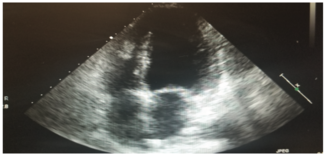

This is a 58-year-old female with a history of tuberous sclerosis. Transthoracic echocardiogram images demonstrated a heterogeneous mass in the mid right ventricle attached to the septum and the moderator band. The mass looked similar to what...